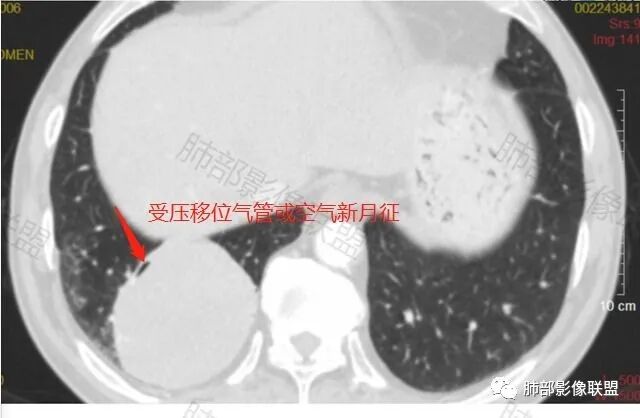

男性,62,胆结石入院胸部CT偶然发现占位。肿标稍增高,右肺下叶胸膜下肿块,边缘尚清,密度较均匀,增强明显强化,血管贴边,空气新月征?静脉期可见低强化区,首先考虑PSP,鉴别肉瘤样癌及神经内分泌肿瘤

右肺下叶肿块,呈外带大内带小的椭圆形改变(内带受支气管及血管挤压原因),边缘光滑,无分叶毛刺,支气管受压,增强后,均匀延迟强化,动脉期见血管贴边,静脉期内部瘤样血管强化区,相邻胸膜无侵犯,纵隔无淋巴结肿大,符合PSP,不鉴别。

胸部CT:右肺下叶一类圆形肿块影,边界清楚,大部分边缘光滑、外缘边界模糊,邻近支气管推移、血管贴边,病灶内可见分枝状血管,平扫密度尚均匀,增强后大部分均匀延迟强化,部分与膈肌黏连、尾征?考虑:类Ca>PSP>SFT。鉴别肉瘤样Ca,CD等。

肿块位于周围(起自细支气管呼吸道上皮),均匀膨胀生长(符合良性的生长特点),病灶内部大部分密度较均匀,部分小低密度不强化区(囊变),增强强化较明显,边缘血管增粗贴边,临近支气管受压,支持PSP。